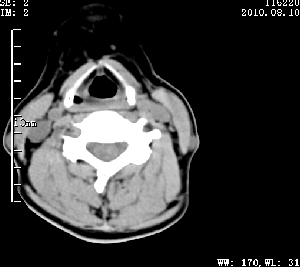

标题: CT28317:病人近几天无意间发现颈部肿块。 [打印本页]

标题: CT28317:病人近几天无意间发现颈部肿块。

甲状腺左叶局限性结节性甲状腺肿可能。建议增强扫描。

病变边界清楚,周围间隙清晰,甲状腺左叶(甲状旁腺?)肿大,右叶甲状腺腺瘤。

病变边界清楚,周围间隙清晰,左叶甲状腺肿大,右叶甲状腺小腺瘤。